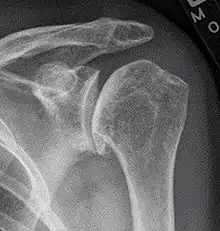

| Diagram of the human shoulder joint | |